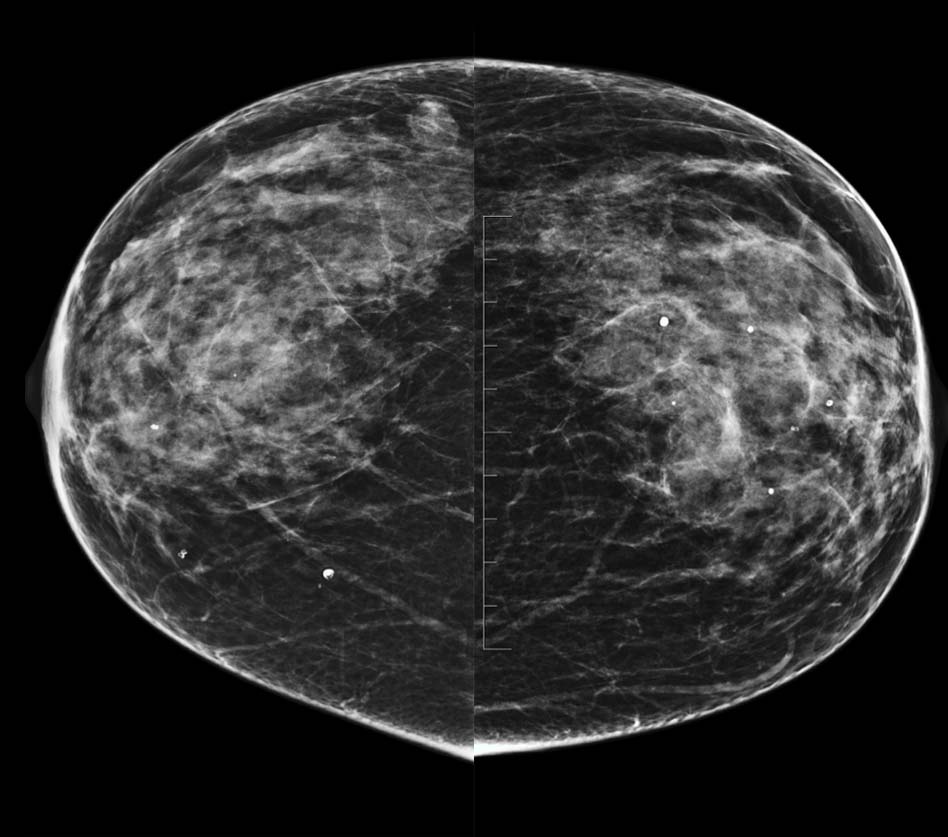

- Control previo en el PPDCMA (Programa de Prevención del Cáncer de Mama en Aragón) en 2019 normal. Control actual en las imágenes.

- A. BI-RADS 0. Hay que completar estudio con RM con contraste.

- B. BI-RADS 1. No hay que hacer nada porque el nódulo tiene aspecto benigno.

- C. BI-RADS 4. Haremos biopsia con aguja gruesa (BAG) del nódulo.

- D. BI-RADS 2. Haremos punción con aguja fina (PAAF) del nódulo.

- E- BI-RADS 3. Control con ecografia mamaria en 6 meses.